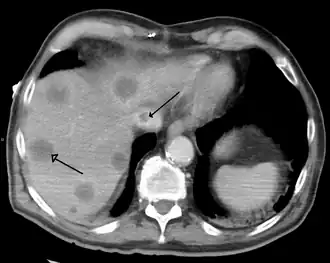

| Síndrome de Budd-Chiari secundária a um câncer. Note o coágulo na veia cava inferior e a metástase no fígado | |

A síndrome de Budd-Chiari é mais habitualmente diagnosticada usando-se ultrassonografia abdominal e tomografia computadorizada helicoidal/multislice do abdome. O ultrassom pode mostrar a obliteração das veias hepáticas, trombose ou estenose, grandes vasos colaterais ou um cordão hiperecoico substituindo uma veia normal. A tomografia mostra a presença do trombo no interior dos vasos e/ou a ausência de fluxo vascular.